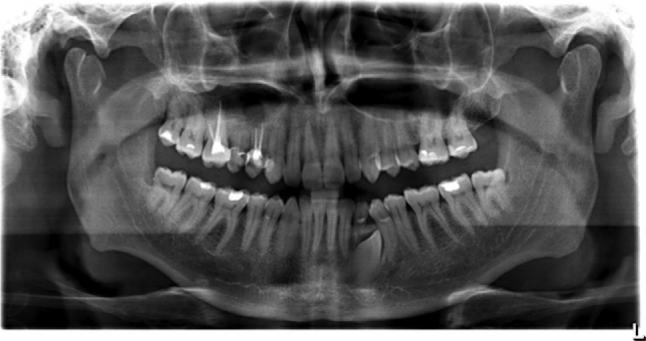

Foreign bodies found in the maxillary sinus include tooth roots, burs, dental impression material, root-filling materials, dental implants, and needles. The purpose of this paper was to present an unusual case of a large foreign body of endodontic origin (root-filling material) removed from the maxillary sinus. A 45-year-old generally healthy male patient reported to the Department of Conservative Dentistry with Endodontics of the Medical University of Silesia, because of orbital and buccal pain on the right side of his face and headaches in the preceding 6 months. Those symptoms were associated with the end of endodontic treatment of teeth 14 and 16. Periapical X-rays, including of teeth 14 and 16, showed the presence of root canal filling with extrusion of endodontic obturation material beyond the apices of tooth 14. In the case of tooth 16, a completely filled palatal canal and incompletely filled buccal canals were found. There was also an irregular dimness at the upper edge of the X-ray image. Panoramic radiography and computed tomography demonstrated a foreign body in the right sinus. Sinus exploration was performed via a surgical procedure conducted using topical anesthesia. The root apices of tooth 14 were resected, and foreign substance was removed. The practitioner did not correctly recognize a complication that occurred during endodontic treatment, which resulted in extrusion of endodontic material beyond the root apices of tooth 14. This case emphasizes the potential impact that an involved maxillary sinus may have on endodontic therapy. Detailed diagnostic identification based on the medical interview, physical and histopathological examinations, and diagnostic imaging allowed rapid surgical intervention and prevented local and general complications. It is important to realize that the range of the periapical X-ray projection is not always sufficient.

在上颌窦中发现的异物包括牙根、牙钻、牙科印模材料、根管充填材料、牙种植体和针头。本文的目的是介绍一例罕见的源自牙髓治疗的大型异物(根管充填材料)从上颌窦取出的病例。一名45岁的健康男性患者因右侧面部眼眶和颊部疼痛以及前6个月的头痛,前往西里西亚医科大学保守牙科与牙髓病科就诊。这些症状与14号和16号牙齿的牙髓治疗结束有关。包括14号和16号牙齿在内的根尖X线片显示根管充填,牙髓充填材料超出了14号牙齿根尖。对于16号牙齿,发现腭根管完全充填,颊根管充填不完全。X线图像上缘还存在不规则的模糊影。全景X线摄影和计算机断层扫描显示右侧上颌窦有异物。通过局部麻醉下的外科手术进行鼻窦探查。切除了14号牙齿的根尖,并取出了异物。该从业者未正确识别牙髓治疗期间发生的并发症,导致牙髓材料超出14号牙齿根尖。该病例强调了受累上颌窦可能对牙髓治疗产生的潜在影响。基于医学问诊、体格检查、组织病理学检查和诊断成像进行详细的诊断识别,有助于快速进行手术干预并预防局部和全身并发症。必须认识到根尖X线投影范围并不总是足够的。